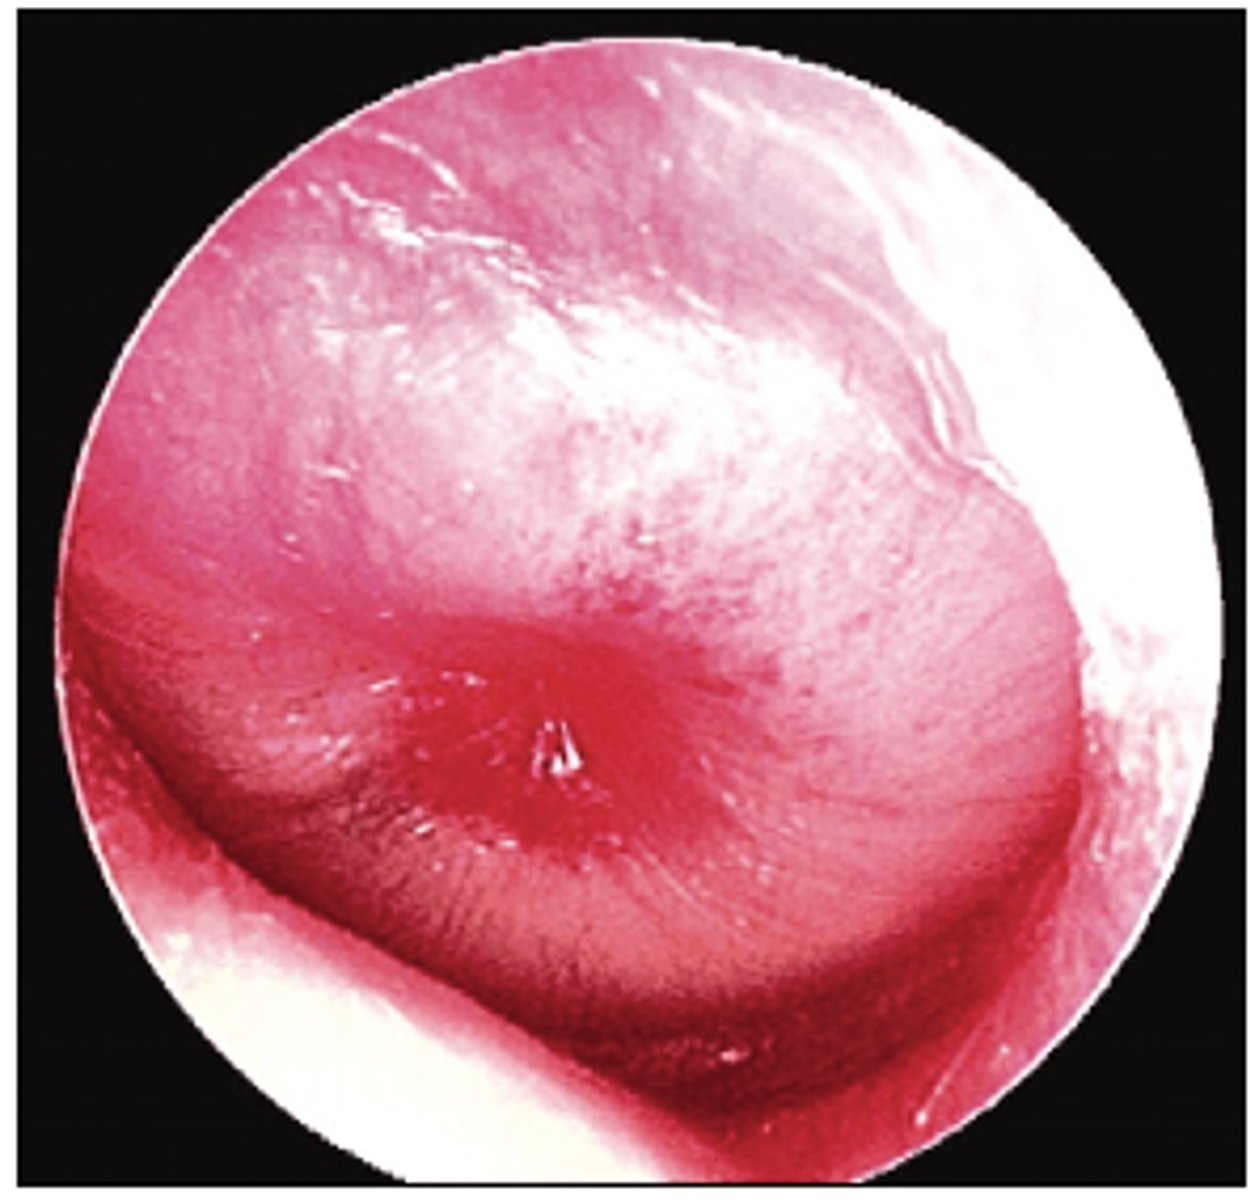

Image shows Bullous Myringitis

What does the image indicate?

Bullous Myringitis

-Blisters and small lumps on eardrum

-May be partial hearing loss for 2-3 days

-Agents: Mycoplasma & S. Pneumonia

-TX: Oral macrolides; oral or ear drop analgesics; lancing may be necessary